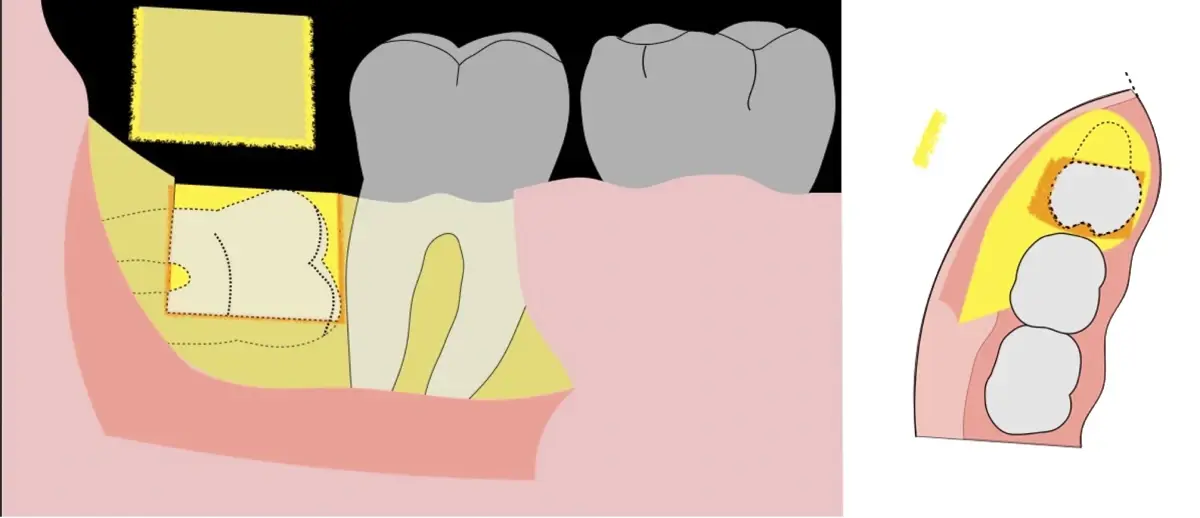

El procedimiento se inicia colocando anestesia troncular para bloqueo del nervio dentario inferior y sus ramas. Luego, se establecerá el diseño de acceso según la disposición de la molar a extraer. Para fines didácticos, se explicará cómo se realizaría la extracción de la molar de la Figura 1: se realiza una incisión horizontal a nivel de la zona retromolar hasta llegar a distal de la segunda molar, continuándose con una incisión intrasurcular hasta mesial de la segunda molar, finalizando con una incisión vertical a espesor total hasta llegar a la línea mucogingival (Figura 2).